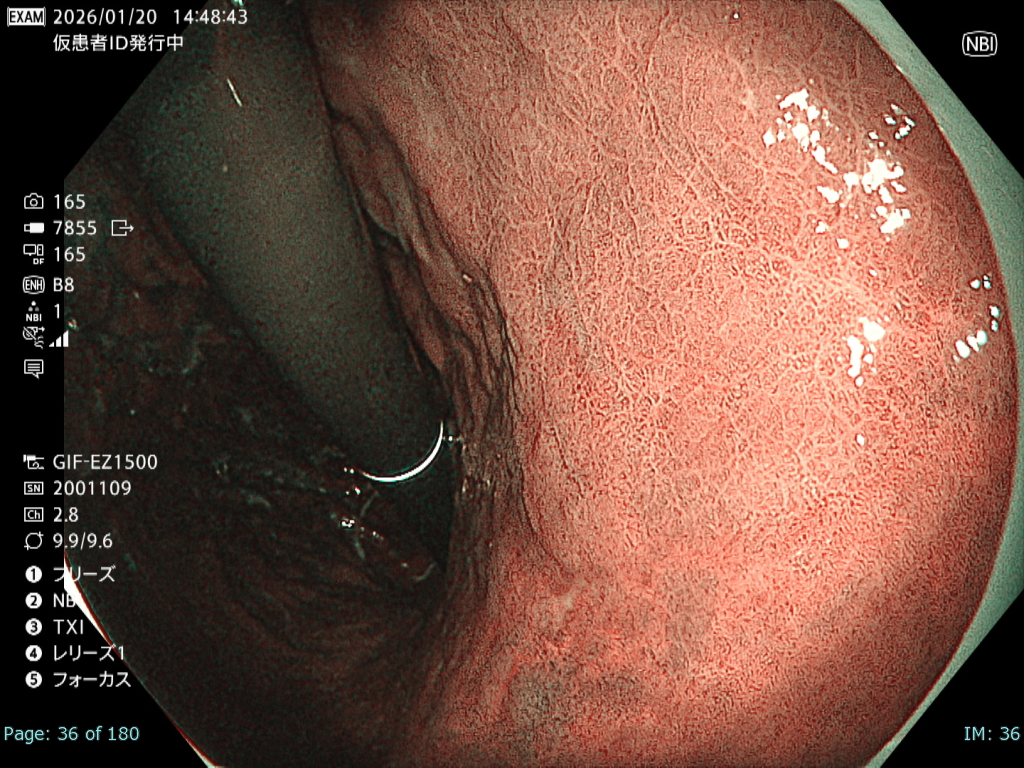

• 白色光観察①(近景)

強調設定:A7

図2

本病変は易出血性であり、血液洗浄後に観察・撮影できる時間は極めて短かったが、表面構造および色調を損なうことなく病変が明瞭に描出されている。記録画像として再評価にも十分耐え得る内視鏡画像である。